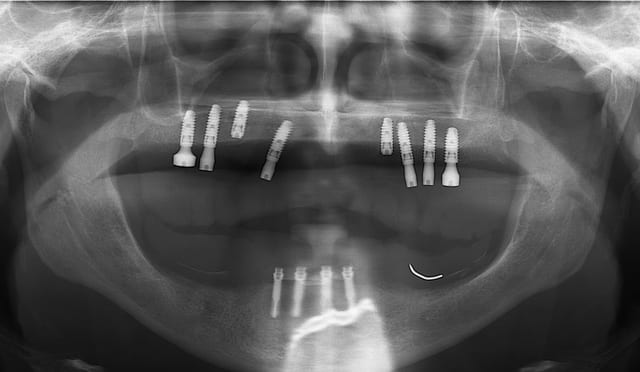

vis de cicatrisation sur une expansion réalisée en mars 09 à Sallanches implants en 13/14/15/18 pour une barre et PT.

Interessante car fracture de l'os vestibulaire y compris de la bosse canine, vitalos mais pas de vis d'ostéosynthese, et comme je sais que le doute est toujours present, ouverture large, avec décollement plus que necessaire pour controle.

sur l'implant en 14 une feuille d'os , en 13 un petit creux en mesio vestibulaire et 15 nickel.

il ne s'agit pas de montrer que cette technique est la seule, mais juste que dans ce cas tout va bien.

merci Thomas je suis bien rentré (croisé 6 paires de "jumelle" avec des habits bleus, mais à chaque fois coup de bol...)et je ne résiste pas au plaisir de passer le pano de notre ami.

Bien sur c'est du travail "d'amateurs", les axes sont nuls mais il semblerait que ton patient va l'avoir son amovo-inamovible!